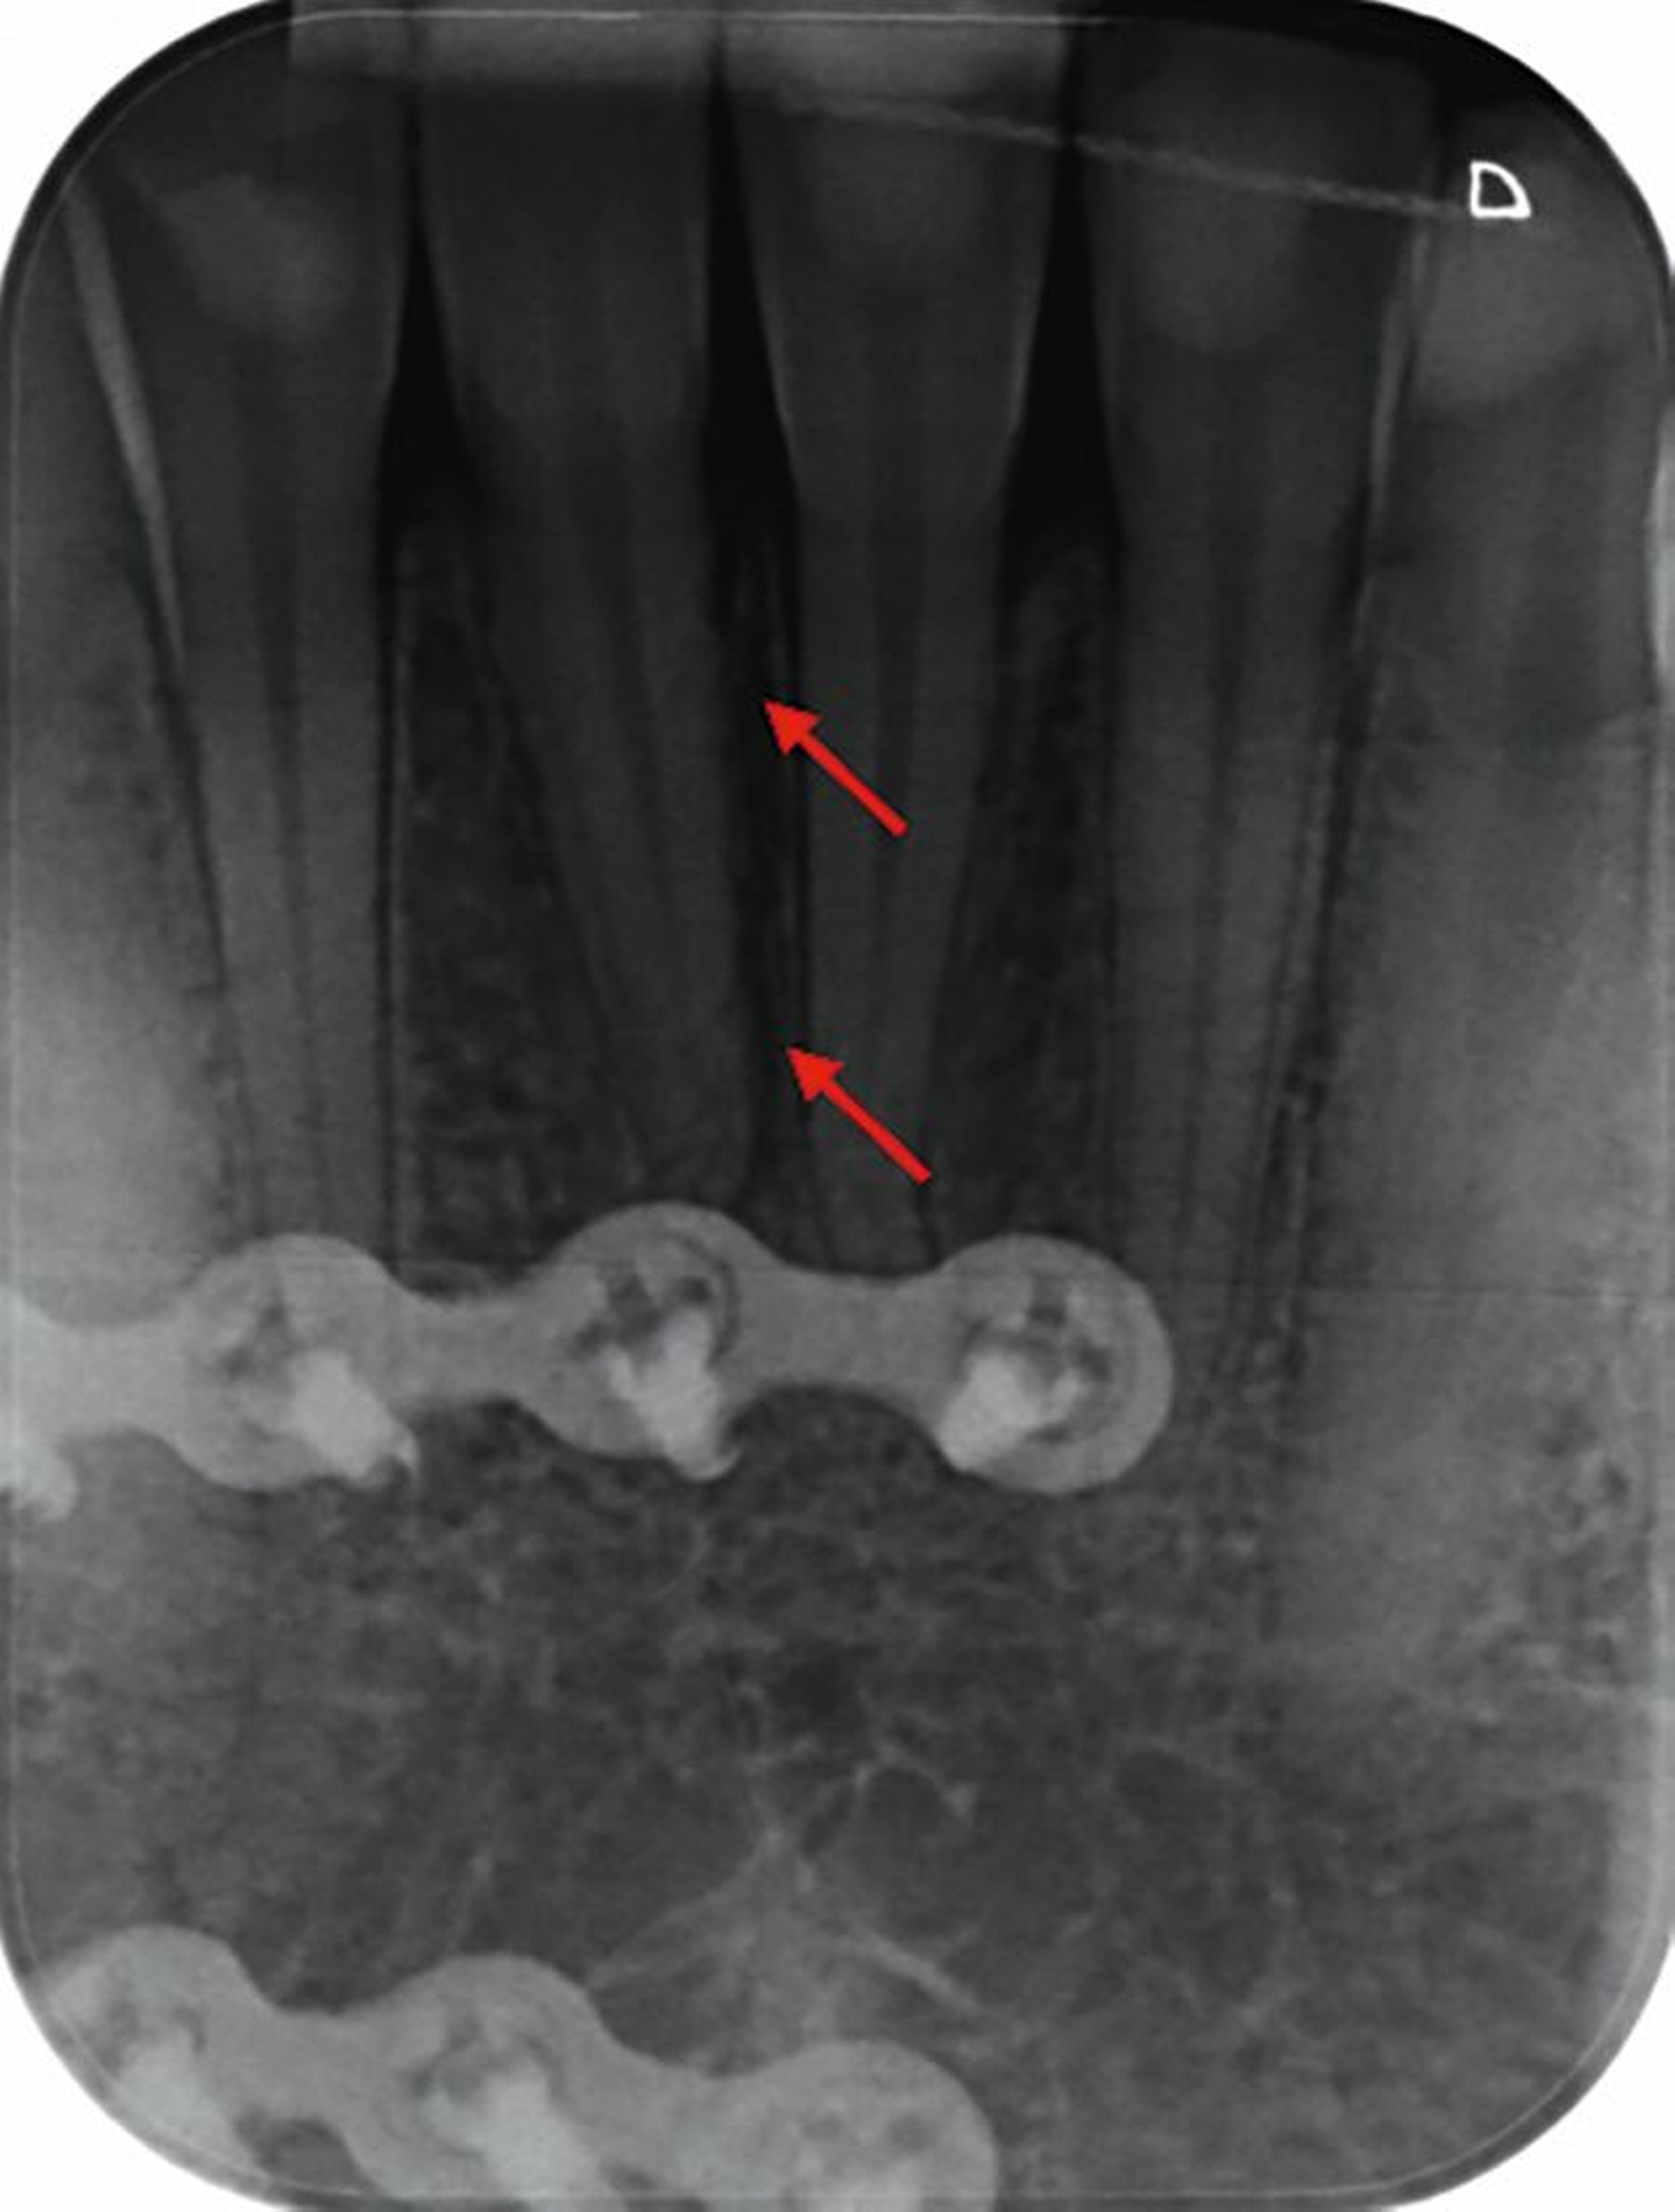

Zunächst wurden Einzelbildaufnahmen der Zähne 24, 26, 35, 33–43 angefertigt. Dabei fiel eine transluzente Frakturlinie ausgehend vom mesialen Parodontalspalt des 41 auf, die sich nach apikal-distal bis zum Apex des 42 darstellte (Abbildungen 3 und 4). Für einen radiologischen Überblick, mit dem auch eine Kiefergelenksfraktur ausgeschlossen werden kann, wurde eine Panoramaschichtaufnahme herangezogen (Abbildung 5). Darauf bildete sich eine unscharfe, C-förmige Transluzenz apikal der Zähne 31 und 41 ab. Eine genaue Beurteilung war nicht möglich, da der Bereich apikal der Unterkieferfront außerhalb der Bildebene lag. Die Processus coronoidei und condylares stellten sich beidseits unauffällig dar. Die Verdachtsdiagnose lautete: Unterkieferfraktur, unkomplizierte Kronenfrakturen an den Zähnen 26 und 35 sowie eine Längsfraktur an Zahn 24.